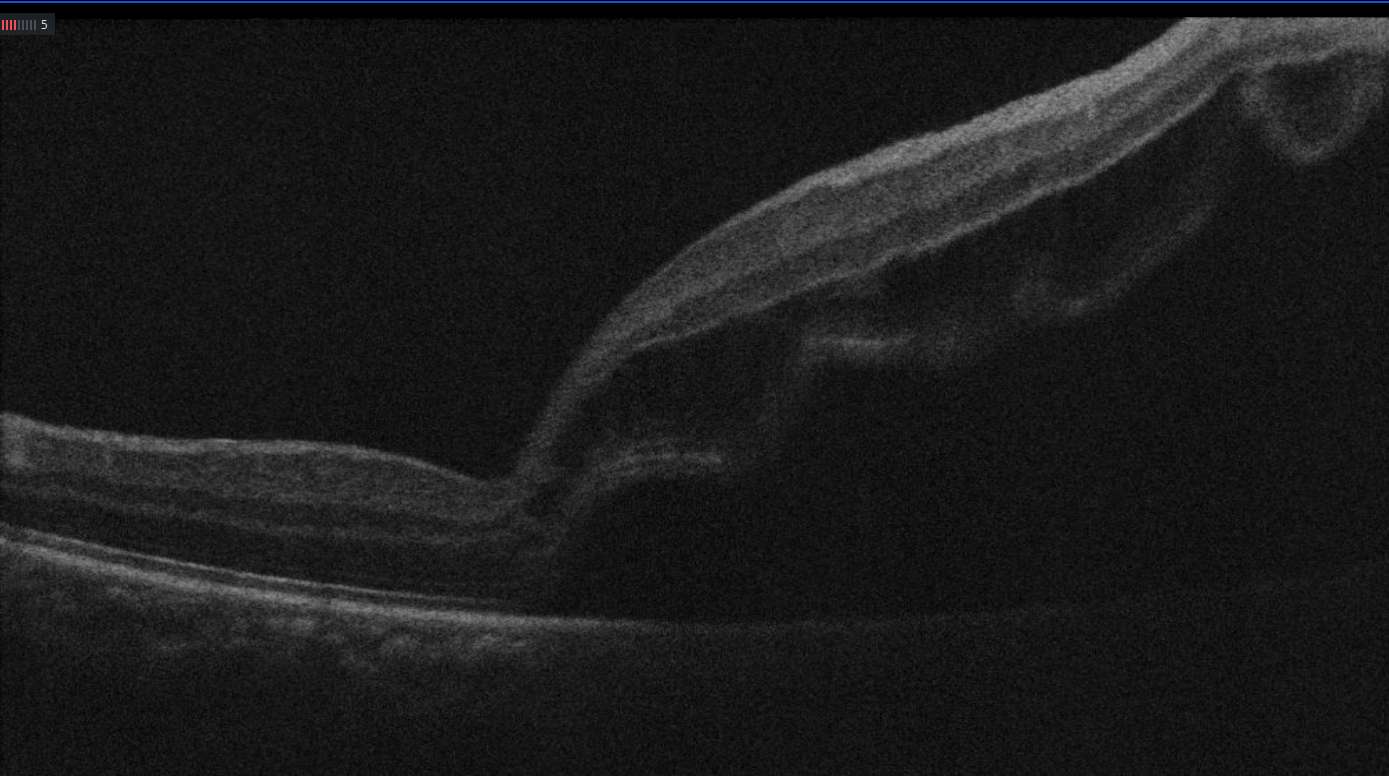

小陈和父亲来到了龙岗区耳鼻咽喉医院刘清云主任的诊室,刘主任为小陈检查时发现右眼视网膜脱离的范围很大,在9点位-1点位视网膜青灰色隆起,累及黄斑区,中央动静脉随视网膜隆起、变形,12点位周边部视网膜见1个圆形裂孔,大小约0.1PD,10点至11点半周边部视网膜见视网膜格子样变性区。

刘清云主任考虑到患者很年轻,玻璃体尚未液化,凝胶状态完整,裂孔在视网膜周边,巩膜扣带术(外路法)不切除玻璃体,保持眼球内部的自然结构,对患者来说较为合适,从住院到手术,在短短的17小时内,刘主任为小陈完成了高难度的视网膜脱离复位术,术后第一天右眼的视网膜平伏,裂孔也已经封闭了,恢复良好,小陈和父亲悬着的心终于放下了。